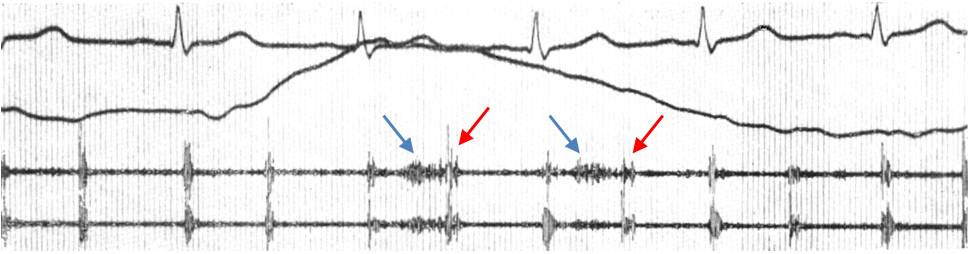

Кардиопульмональный (пульмокардиальный) шум. Везикулярный шум, усиливающийся в ритме сердечных сокращений вследствие дополнительного расширения участка легкого, примыкающего к сердцу, во время систолы желудочков (рис. 9). Он чаще слышен слева вдоль границы относительной тупости сердца, иногда в межлопаточном пространстве, исчезает при задержке дыхания.

Рис. 9. Кардиопульмональный шум.

Сверху вниз: ЭКГ II отведение. Пневмограмма. ФКГ В1 и С2. В двух первых и двух последних сердечных циклах (выдох) тоны без особенностей, шума нет. На вдохе II тон расщеплен с интервалом 0,4 с (красные стрелки), появляется высокочастотный мезосистолический шум (синие стрелки), приближающийся к веретенообразному.